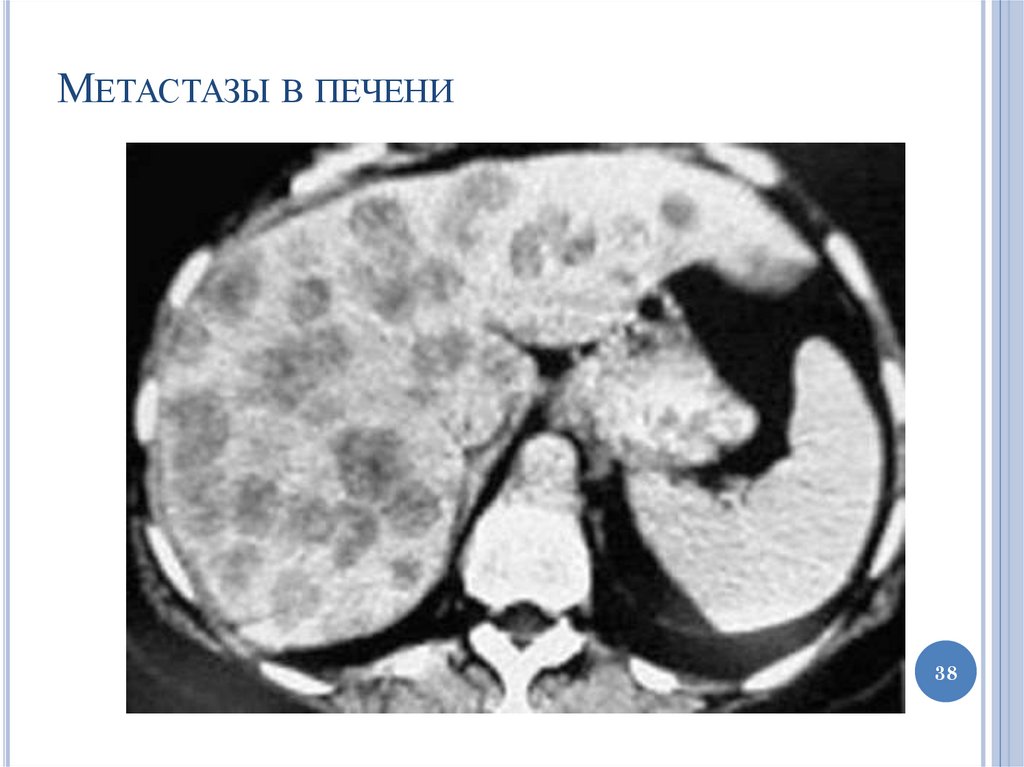

38.

МЕТАСТАЗЫ В ПЕЧЕНИ

38